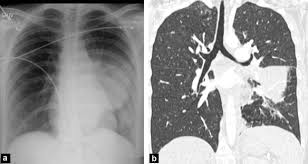

Black Hole In The Lung Bone Marrow Transplantation

Black Hole In The Lung Bone Marrow Transplantation from media.springernature.com